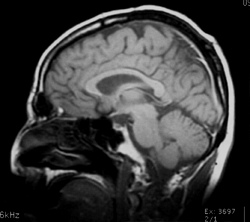

Figure 20: A picture of the human brain. |

The link between warm-bloodedness and large brain size is fairly indirect. Brain tissue is vulnerable to changes in temperature. Human brains addle when heated to 108 degrees Fahrenheit even for a few minutes, and higher cerebral functions become erratic when the brain is chilled below 90 degrees Fahrenheit. So warm-bloodedness and a constant body temperature are prerequisites for a large brain. It may be that warm-bloodedness evolved first, and the evolution of large brains followed. (Bakker, 1986) |